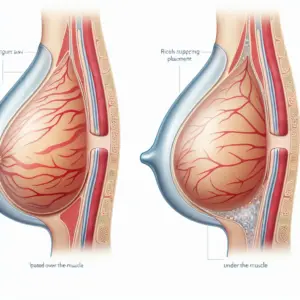

A melhor cirurgia para levantar as mamas varia conforme o grau de ptose, volume e pele, com técnicas específicas para cada caso. Avaliação médica personalizada é essencial para resultados naturais e satisfatórios.